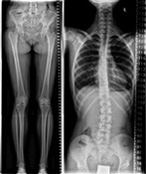

We are very satisfied with the image quality for both, spine and legs, when we use the stitching feature at the CombiDiagnost R90 table."

Claude Scholtes

Head of Radiology, Centre Hospitalier du Nord (CHdN), Ettelbruck, Luxembourg.